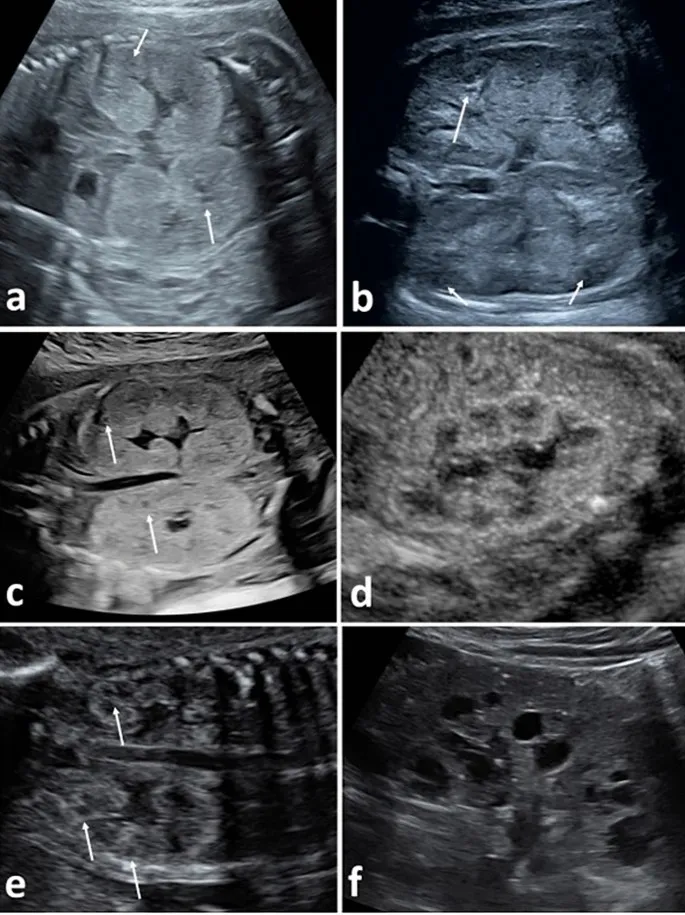

- Pathophysiology: Numerous cysts in all parts of the nephron cause bilateral, massive kidney enlargement.

- Bilaterally enlarged, echogenic kidneys with a smooth surface.

- Cysts are elongated, arising from collecting ducts and arranged radially.